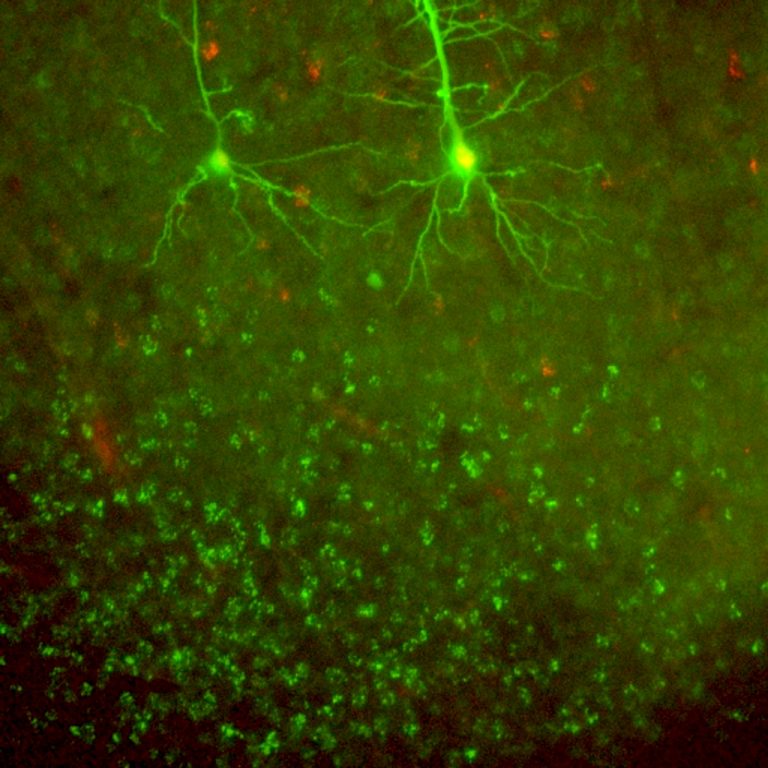

Cellule staminali contro il Parkinson

3

Claudia De Luca